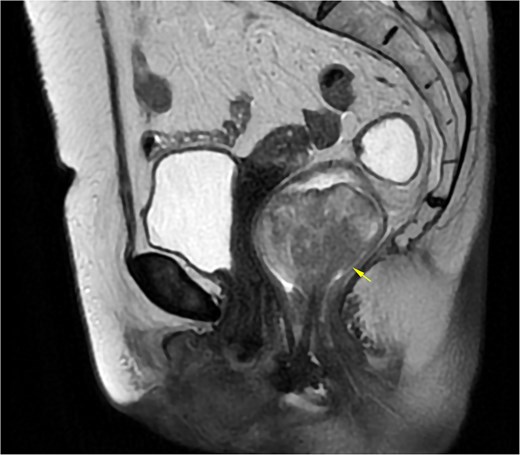

A 69-year-old woman with no significant medical history presented with rectal bleeding and a manually reducible prolapsed tumor for the past 3 months. A colonoscopy revealed a black, pedunculated tumor with a base at 6 o’clock, located along the pectineal line, measuring 5 cm in diameter, with erosion and signs of recent bleeding. Biopsy confirmed malignant melanoma. Before admission, the patient experienced anal pain and observed that the tumor had become irreducible. On examination, the tumor was pedunculated, irreducible, mobile, soft in consistency, black in color, and emitted a putrid odor (Fig. 1). Blood tests showed hemoglobin at 9.4 g/dl and a C-reactive protein level of 34.9 mg/l. A magnetic resonance imaging (MRI) study showed a well-defined rectal mass measuring 53 × 47 × 44 mm, with no regional lymph node involvement (Fig. 2). The computerized tomography (CT) scan showed no distant metastases. The multidisciplinary committee decided on WLE. Postoperative recovery was uneventful, and the patient was discharged after 48 h.

MRI of Case 1 shows a well-defined rectal tumor without regional lymph node involvement. The lesion demonstrates high signal intensity on sagittal T2-weighted imaging (indicated by the arrow).